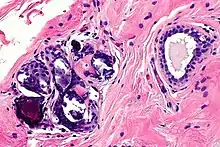

Mechanical+Enzymatic(ME) and mechanical methods are the most common isolation methods, although there is no standard method.[11] Accordingly, Dr. Glass and Ferretti proposed one of the ME methods which is to apply tumescent-assisted liposuction using a mechanical or ultrasound-assisted liposuction cannula. Through liposuction, the fat sample is digested by enzymatic activities of collagenase or trypsin in Dulbecco’s modified Eagle's medium (DMEM). The resultant tissue suspension undergoes incubation and agitation at around 37 °C and is filtered through a strainer to remove unnecessary debris. The cell pallet left after centrifugation is called SVF. The SVF is seeded on the plate, after the second suspension with bovine calf serum, 1% penicillin or streptomycin, and L-glutamine. The adherent properties of ADSCs on the plate allow isolation of ADSCs.[12] However, due to the inconvenience of isolating the pure ADSCs, a cell-assisted lipo-transfer (CAL) is more commonly used. CAL transforms poor ADSCs into enriched ADSCs by mixing isolate SVF and aspirated fat.[13] The efficacy of CAL was proven by the increased survival rate of autologous breast augmentation when introduced around 270ml for each breast.[14]